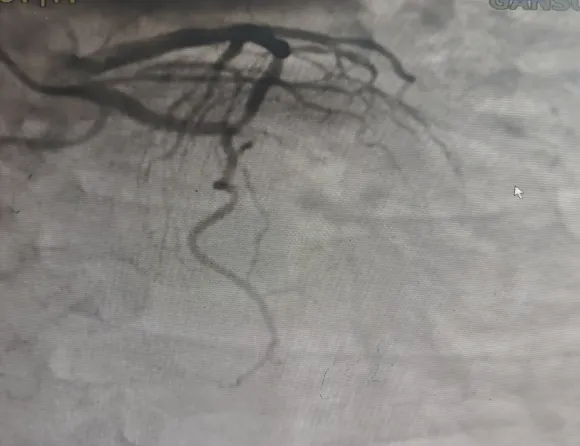

近日我科成功救治的急性心肌梗死患者,男,48岁,主因“突发胸痛4小时”由120送至我院。绕行急诊和CCU第一时间到达导管室。在救护车上给与胸痛一包药和普通肝素。既往无高血压,糖尿病史,无吸烟史。家族史正常。成功开通闭塞回旋支后患者症状改善,心功能恢复。

患者冠脉造影检查,术前术后图